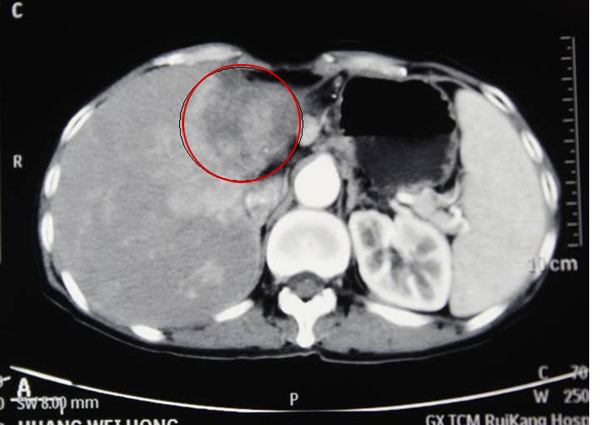

2013年7月,黄阿姨在我院被确诊为肝内胆管细胞癌,肝肿块鸭蛋大。在来我院治疗之前,已经辗转多家医院,病情都没有得到很好的控制。“3年前因为上腹部连腰部剧烈疼痛,到区内一家医院治疗,诊断我是‘肝肿瘤’,经过治疗,疼痛不仅没有缓解反而加剧。之后1年我四处求医,但希望最终都化为泡影,好几次因忍受不了疼痛想放弃治疗,放弃生命,偶然的机会医生介绍我到了瑞康医院。”

治疗前

肝癌射波刀治疗后肿块消失